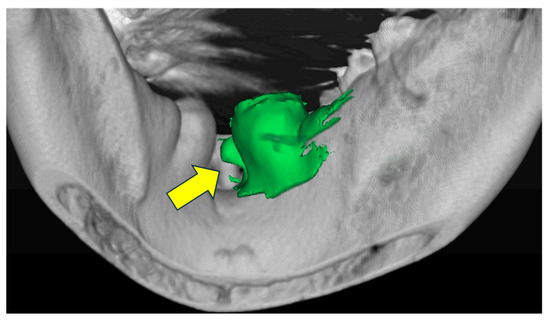

2.2. Classification of Morphology and Size